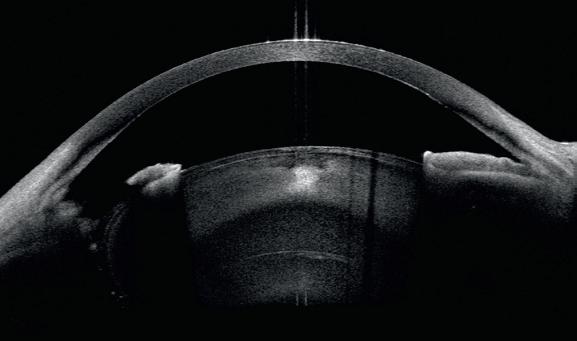

This concerns a patient with bilateral Fuchs’ dystrophy whose history includes DSAEK surgery in the right eye with subsequent ocular hypertension due to misdirection syndrome, requiring pars plana Vitrectomy and Goniosynechialysis in the same procedure. The patient presented significant photophobia and cataract, with intraocular pressure of 18 mmHg (figure 1).

CASIA2 images inform us about corneal transparency and good adaptation of the endothelial graft, but also allows us to visualise the integrity of the lens after inferior iridectomy and gives us a 360° visualisation of the iridocorneal angle (figure 2).

Figure 1